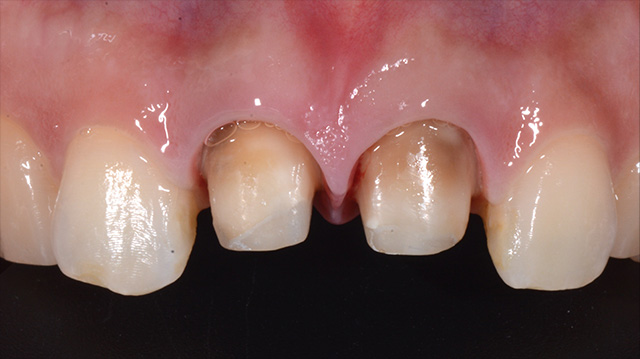

| 年代・性別 | 50代 男性 |

|---|---|

| 主訴 | 転倒して歯が割れた |

| 治療回数 | 3回 |

| 治療期間 | 約1ヶ月 |

| 費用 | 仮歯 5,500円 ジルコニアクラウン 176,000円 |